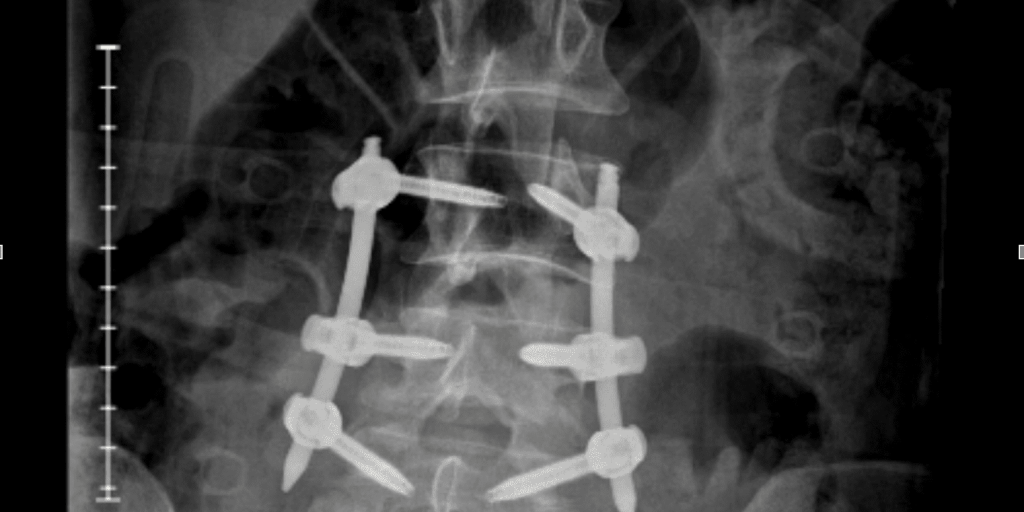

I Broke My Back. The Hardest Part Has Been Learning to Live Again. – Social Lifestyle Magazine

On the night of June 15, 2025, my life split in two: Before the fall. And after. I wasn’t being reckless. It wasn’t a dare or some wild stunt....